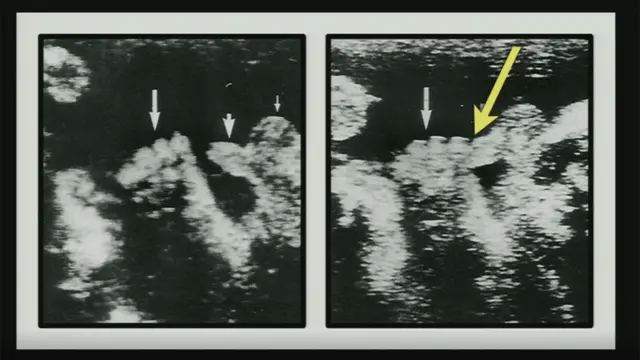

"Les voy a mostrar un par de imágenes de un artículo muy divertido de la Revista de Ultrasonido de Medicina. Me voy a aventurar en decir que es el artículo más divertido que se haya publicado en la Revista de Ultrasonido de Medicina. El título es 'Observaciones de masturbación en el útero'".

Y, a continuación, Mary Roach proyecta sobre la pared del escenario una ecografía en la que se ve, claramente, un feto con la mano aferrada al pene.

No olvidemos que se trata de una ecografía, por lo que "las imágenes se habrían visto en movimiento", le aclara la periodista científica con claras dotes de comediante a la audiencia, que no tiene claro aún si debe reírse a carcajadas o tomarse el tema en serio.